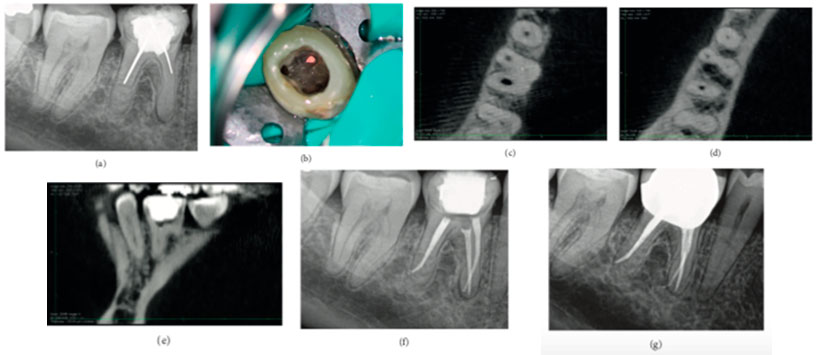

Recientemente, se recomendó el uso intraoperatorio de FOV limitado para la identificación intracamatoria y la localización de canales calcificados; sin embargo, no se informó una técnica clínica para la localización exacta del canal calcificado. En el presente estudio, los puntos de gutapercha se utilizan intraoperatoriamente como marcadores, y la distancia entre el marcador y el orificio del canal de patente se calcula en todos los planos del espacio. También se presenta un caso donde se realizó la misma técnica, pero no todos los orificios del canal pudieron identificarse ya que se borraron.En el presente caso es de una paciente de sexo femenino de 47 años de edad fue remitida para la evaluación y el retratamiento de su primer molar mandibular derecho. El examen clínico no reveló síntomas. Las exploraciones periodontales estaban dentro de los límites normales y no había movilidad. El examen radiográfico reveló un tratamiento previo del conducto radicular con conos de plata y radiolucidez periapical del diente. Los conductos mesiales fueron borrados y no visibles (Figura 1 (a)). El diente fue restaurado con una acumulación de resina compuesta. Se estableció un diagnóstico de tratamiento previo del conducto radicular con periodontitis apical asintomática. Se informó al paciente que el retratamiento convencional del conducto radicular seguido de una corona era la mejor opción. El paciente consintió al plan de tratamiento. Los ultrasonidos se usaron para trepar a lo largo del área del istmo en una posición donde se estimó que estaba el orificio del canal mesiobucal. Después de trepar una ranura de 1 mm de profundidad en la posición mesiovestibular del canal, no se pudo ubicar el orificio. Se colocó un punto GP y se compactó en la profundidad del surco (Figura 1 (b)). A continuación, se colocó una bolita de algodón humedecida con hipoclorito de sodio, y la cavidad de acceso se selló temporalmente con 4 mm de Cavit G. El paciente fue referido para un FOV CBCT limitado. La vista axial de la CBCT reveló que el canal estaba ubicado 0.5 mm bucalmente al punto GP, y la calcificación era evidente (Figura 1 (c)). Además, el canal parecía estar patentado 2 mm apicalmente al punto GP (Figura 1 (d)). La vista sagital de la CBCT reveló que el orificio del canal mesiobucal estaba ubicado a 0.5 mm mesialmente al punto GP (Figura 1 (e)). Luego de la instrumentación, la cavidad de acceso se selló con resina compuesta, y se realizó una radiografía postoperatoria (Figura 1 (f)). El paciente fue retirado cada año para seguimiento clínico y radiográfico. A los dos años de seguimiento, el diente estaba asintomático y la curación periapical se observó radiográficamente (Figura 1 (g)).

Con este reporte queda demostrado los beneficios brindados por las tomografía volumétrica de haz cónico para el diagnostico y control de los tratamientos endodonticos.